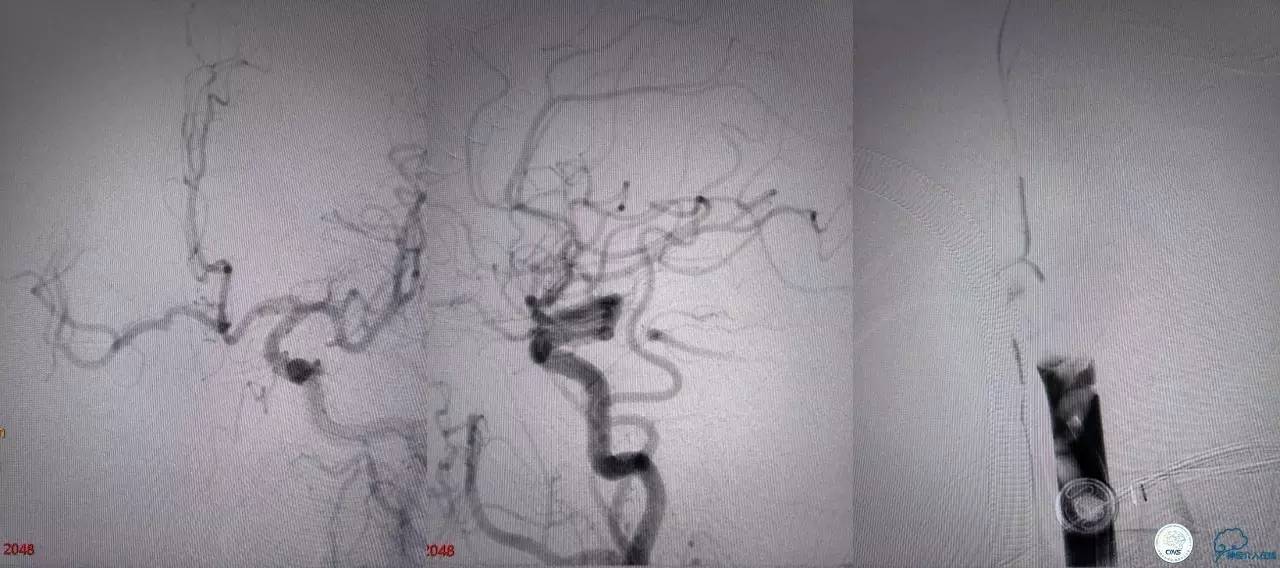

第二次取栓后可见基底动脉顶端仍有大量血栓,右侧大脑后动脉开通,但左侧大脑后未见显影且左侧小脑上动脉闭塞!

第三次取栓,支架放入左侧大脑后取栓。

第三次取栓后,左侧大脑后动脉开通,但是栓子再次栓塞右侧大脑后动脉,血栓在基地动脉顶端来回左右摆动,下一次,怎办?血栓负荷太多,可以使用solumbar技术,可以没有颅内导管,没办法,换用更大的支架6-20mm,但费用增加不少,与家属沟通后同意使用,第四次取栓:

血栓负荷还是很大,左侧大脑后再通,但右侧大脑后又闭塞,只能第五次取栓,支架放到右侧大脑后动脉更远。